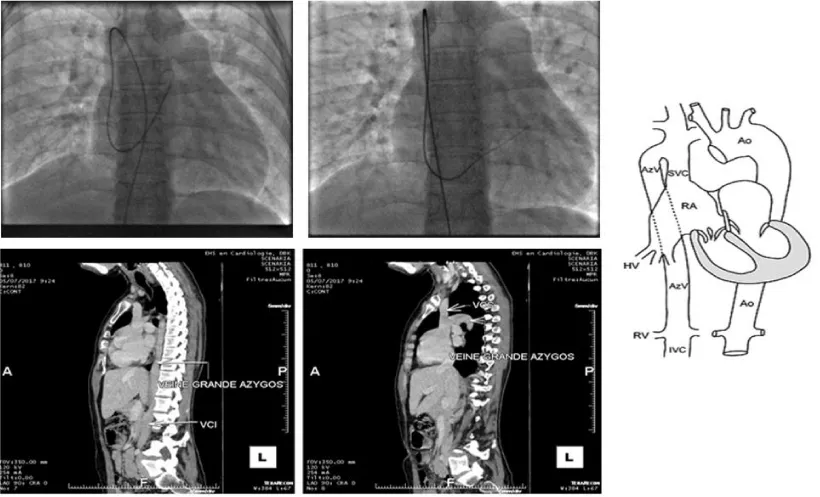

Faced with the desire for pregnancy and with this right cavitary impact and the existence of satisfactory edges (retro-aortic edge 9 mm, posteroinferior edge 10mm, atrioventricular edge 10 mm, upper edge 9 mm, lower cave edge 10 mm, upper cave edge 12 mm) her treating cardiologist decides to entrust her to us for percutaneous closure of this defect (Figure 1).

Figure 1: ASD evaluation before the percutaneous procedure. (A: Right cavities dilatation, B: Tricuspid regurgitation, C-D and E: ASD and edges in TTE, F-G, and H: ASD and edges in TEE).